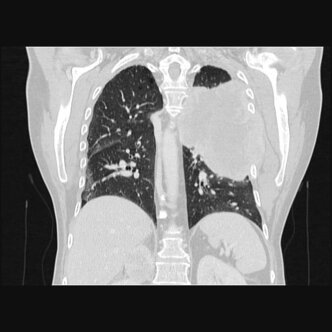

Alle wesentlichen diagnostischen und therapeutischen Verfahren zur Behandlung des Lungenkrebses sind an unserem Klinikum verfügbar z.B. PET-CT, MRT, Endosonographie (EBUS), Chemotherapie, Strahlentherapie, Operation, endoskopische Tumorabtragung und Stentimplantation, Behandlung von Tochtergeschwülsten (Metastasen) u.a. über Neuro- und Viszeralchirurgie oder interventionelle Radiologie.

Die modern ausgestattete Abteilung für Thoraxchirurgie am Städtischen Klinikum Dessau gewährleistet eine optimale Versorgung beim Lungenkrebs als auch bei anderen Erkrankungen im oder am Brustkorb. So werden z.B. Metastasen mit einem hocheffektiven Diodenlaser entfernt und Rippenfrakturen mit Titanklammern stabilisiert.

- Lungenmetastasen (Tochtergeschwülste anderer Tumorerkrankungen) zur Diagnosesicherung oder therapeutischen Entfernung, meist gewebesparend durch Laserchirurgie

- Gutartige Lungenerkrankungen wie Pneumothorax (Lungenriss), Lungenemphysem (Volumenreduktion), Bronchiektasien (Atemwegserweiterung), diagnostische Eingriffe bei unklaren Lungengerüsterkrankungen, in aller Regel minimal-invasiv